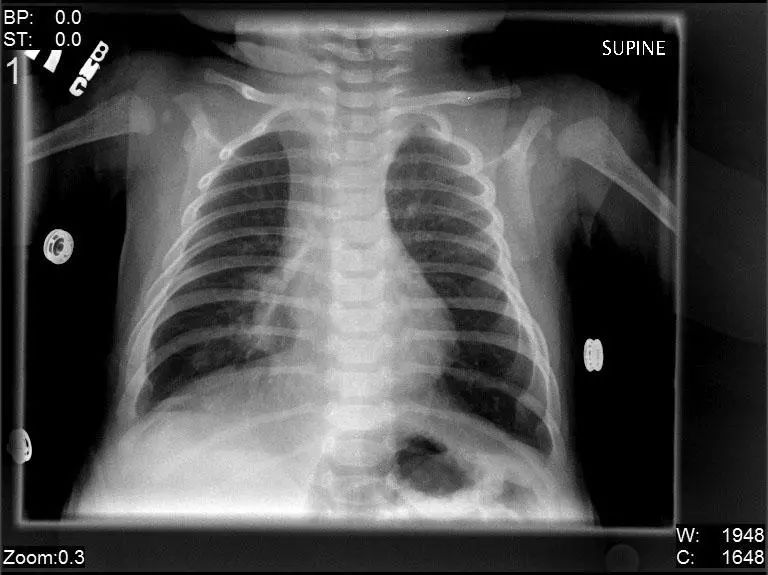

图2.4 2个月龄男孩肺炎患者,右中叶浸润,呼吸道合胞病毒(RSV)感染。